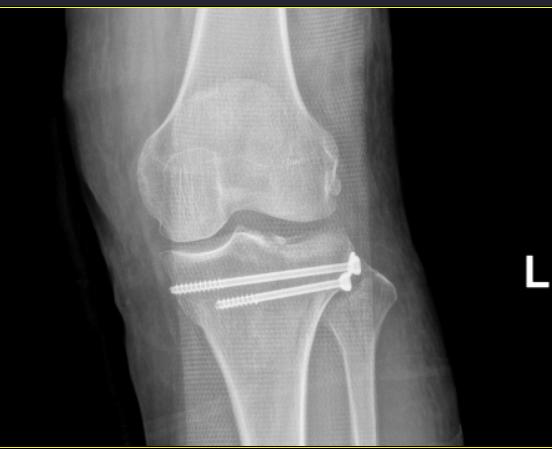

何女士的骨折情况属于上述第①条,经充分的术前准备后,张勇华主任为何女士行“关节镜下胫骨平台骨折复位内固定术”,手术仅切了3个小口,手术顺利,患者恢复非常好,术后3天就出院了。

术后复位

张勇华主任表示,关节镜下骨折复位内固定术有以下明显优点:(1)手术创伤小,能直接观察到关节内结构的损伤;(2)监视关节软骨与骨的复位,提高复位的准确性,避免或减轻创伤性关节炎的发生;(3)确保内固定可靠合理,允许早期不负重的功能训练,防止关节僵直,有助于关节功能的恢复。